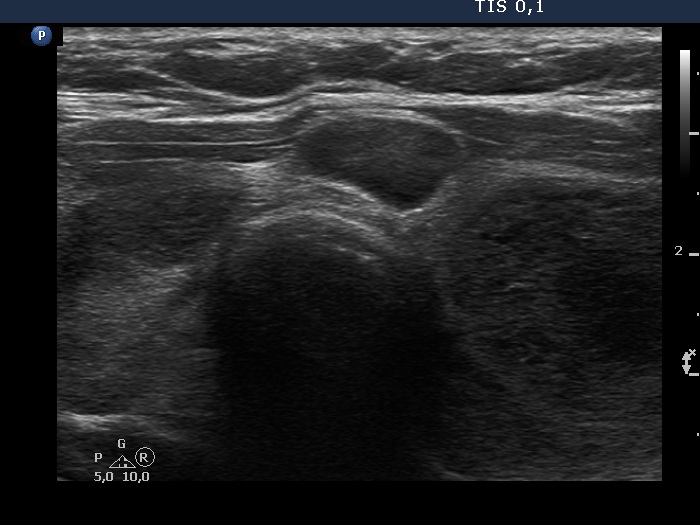

First examination (first, third and fifth rows of images):

Ultrasonography. The thyroid was echonormal and contained multiple inhomogeneous, partly blurred hypoechogenic and moderately hypoechogenic discrete lesions. Multiple lymph nodes were found on both sides of the neck.

Cytology was performed from 3 different thyroid lesions and resulted in a pattern corresponding to non Hodgkin lymphoma.